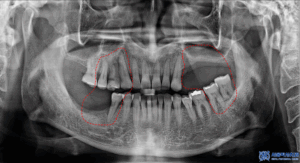

더 정밀히 확인하기 위해,

엑스레이 사진을

찍어보았습니다.

왼쪽 아래 사랑니를 포함한 큰어금니는

맞닿는 위 치아가 없어

정출되어 있는 상황이였고

왼쪽 위는 치아가 없을 뿐 아니라

골흡수가 심하게 진행되어

상악동과의 거리가 가까워져

뼈가 부족한 상황이었습니다.

또한 오른쪽 위 어금니들 역시

치아를 지탱하는 잇몸뼈가

많이 흡수되어 있는 것이

확인되었습니다.